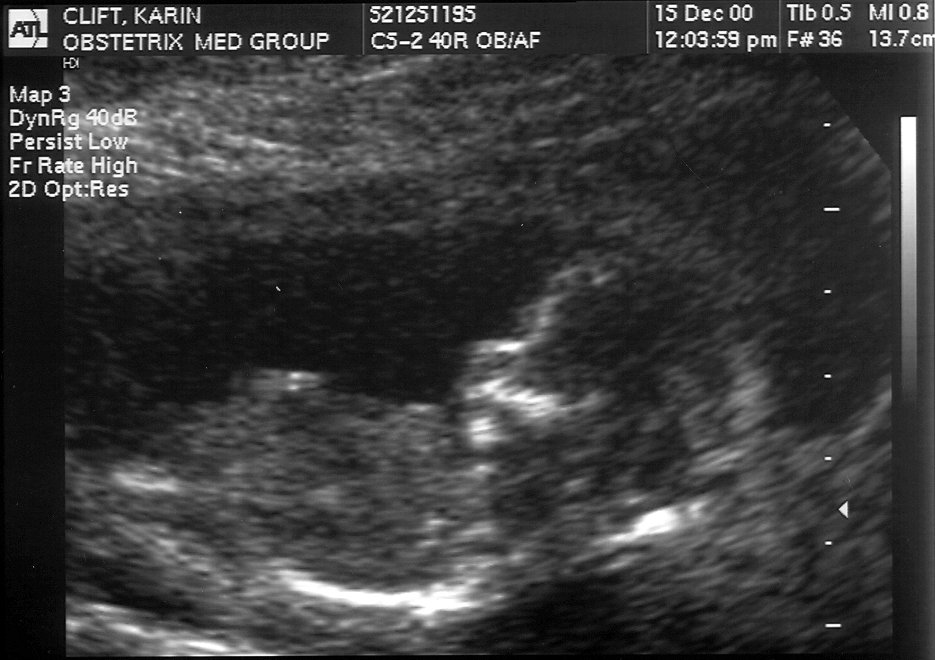

December 15 Amniocentesis results: NORMAL and HEALTHY #1, #2